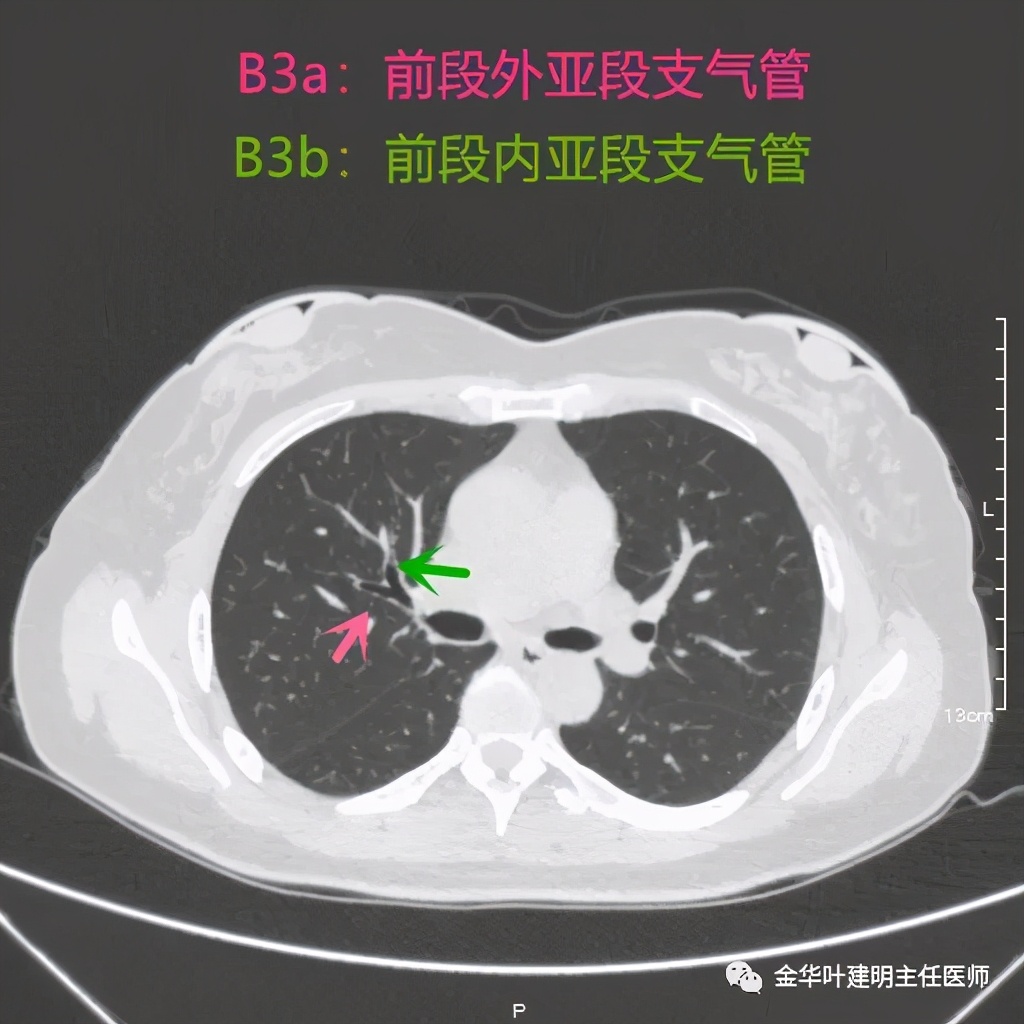

前段:本例前段显示比较清楚,图片较少,我们直接上图:

紫色所指是上叶支气管,红色示前段支气管

上两图示前段的外亚段与内亚段支气管,显示了分叉处